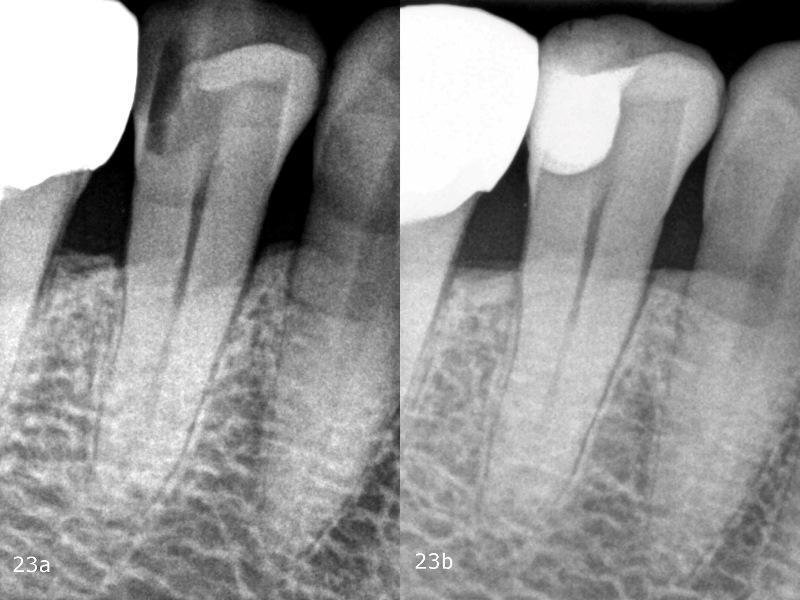

Сравнение предоперационных и послеоперационных рентгенограмм свидетельствует о качестве лечения (фото 23). Благодаря превосходным свойствам термовязкого композита при нанесении реставрация не содержит пузырьков воздуха. Кроме того, два используемых композита однородны с точки зрения видимости на рентгенограммах, и в целом реставрация выглядит однородной, поскольку нет видимых переходов между базовым текучим композитом и композитом с объемной заливкой. Дооперационная рентгенограмма не показала полной протяженности поражения. Только во время лечения стало очевидно, что необходимо провести очень тщательное препарирование, чтобы полностью удалить пораженную структуру зуба. Чтобы сохранить жизнеспособность пульпы, перед фактической реставрацией композитом была проведена десенсибилизация.

Фото 23a-b: Рентгенограмма до и после операции.